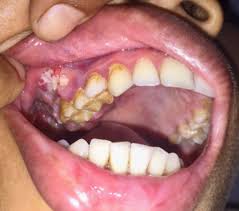

④ 3기

- 특징: 종양의 크기가 4cm 이상이거나, 인접한 림프절로의 전이가 있는 상태입니다.

- 증상: 통증이 심해지고, 삼킴 곤란, 턱이나 목의 부종 등이 나타날 수 있습니다.

- 5년 생존율: 약 55% 이상